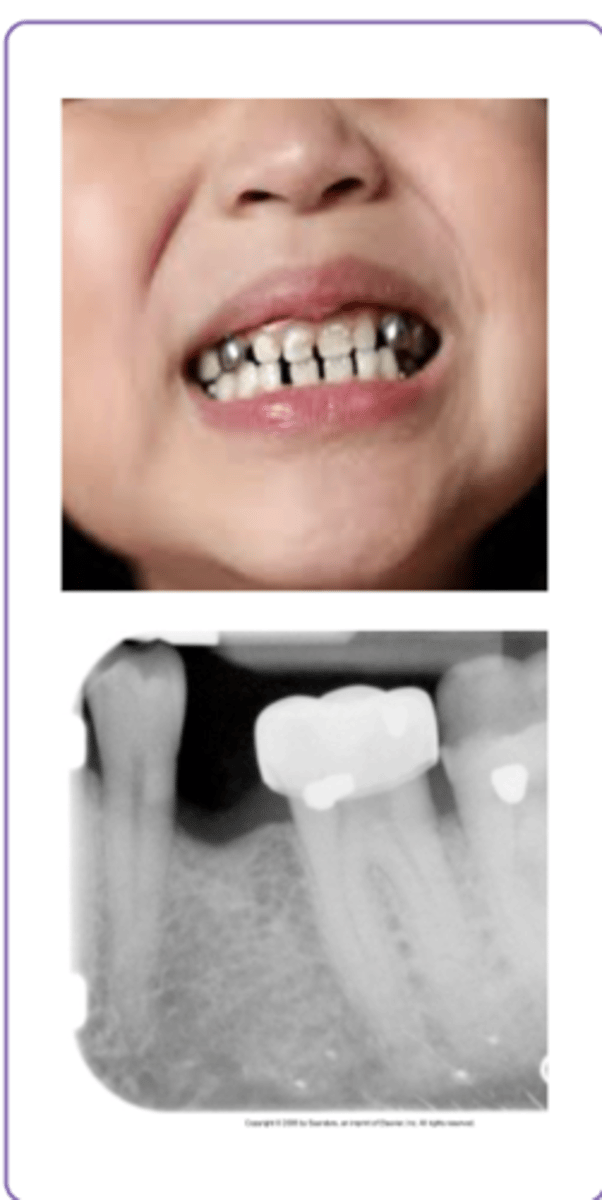

Stainless steel crowns

- Prefabricated metal crowns usually seen in children

- Radiopaque but not as dense as an amalgam or gold

- > Sometimes may be able to see thru to tooth